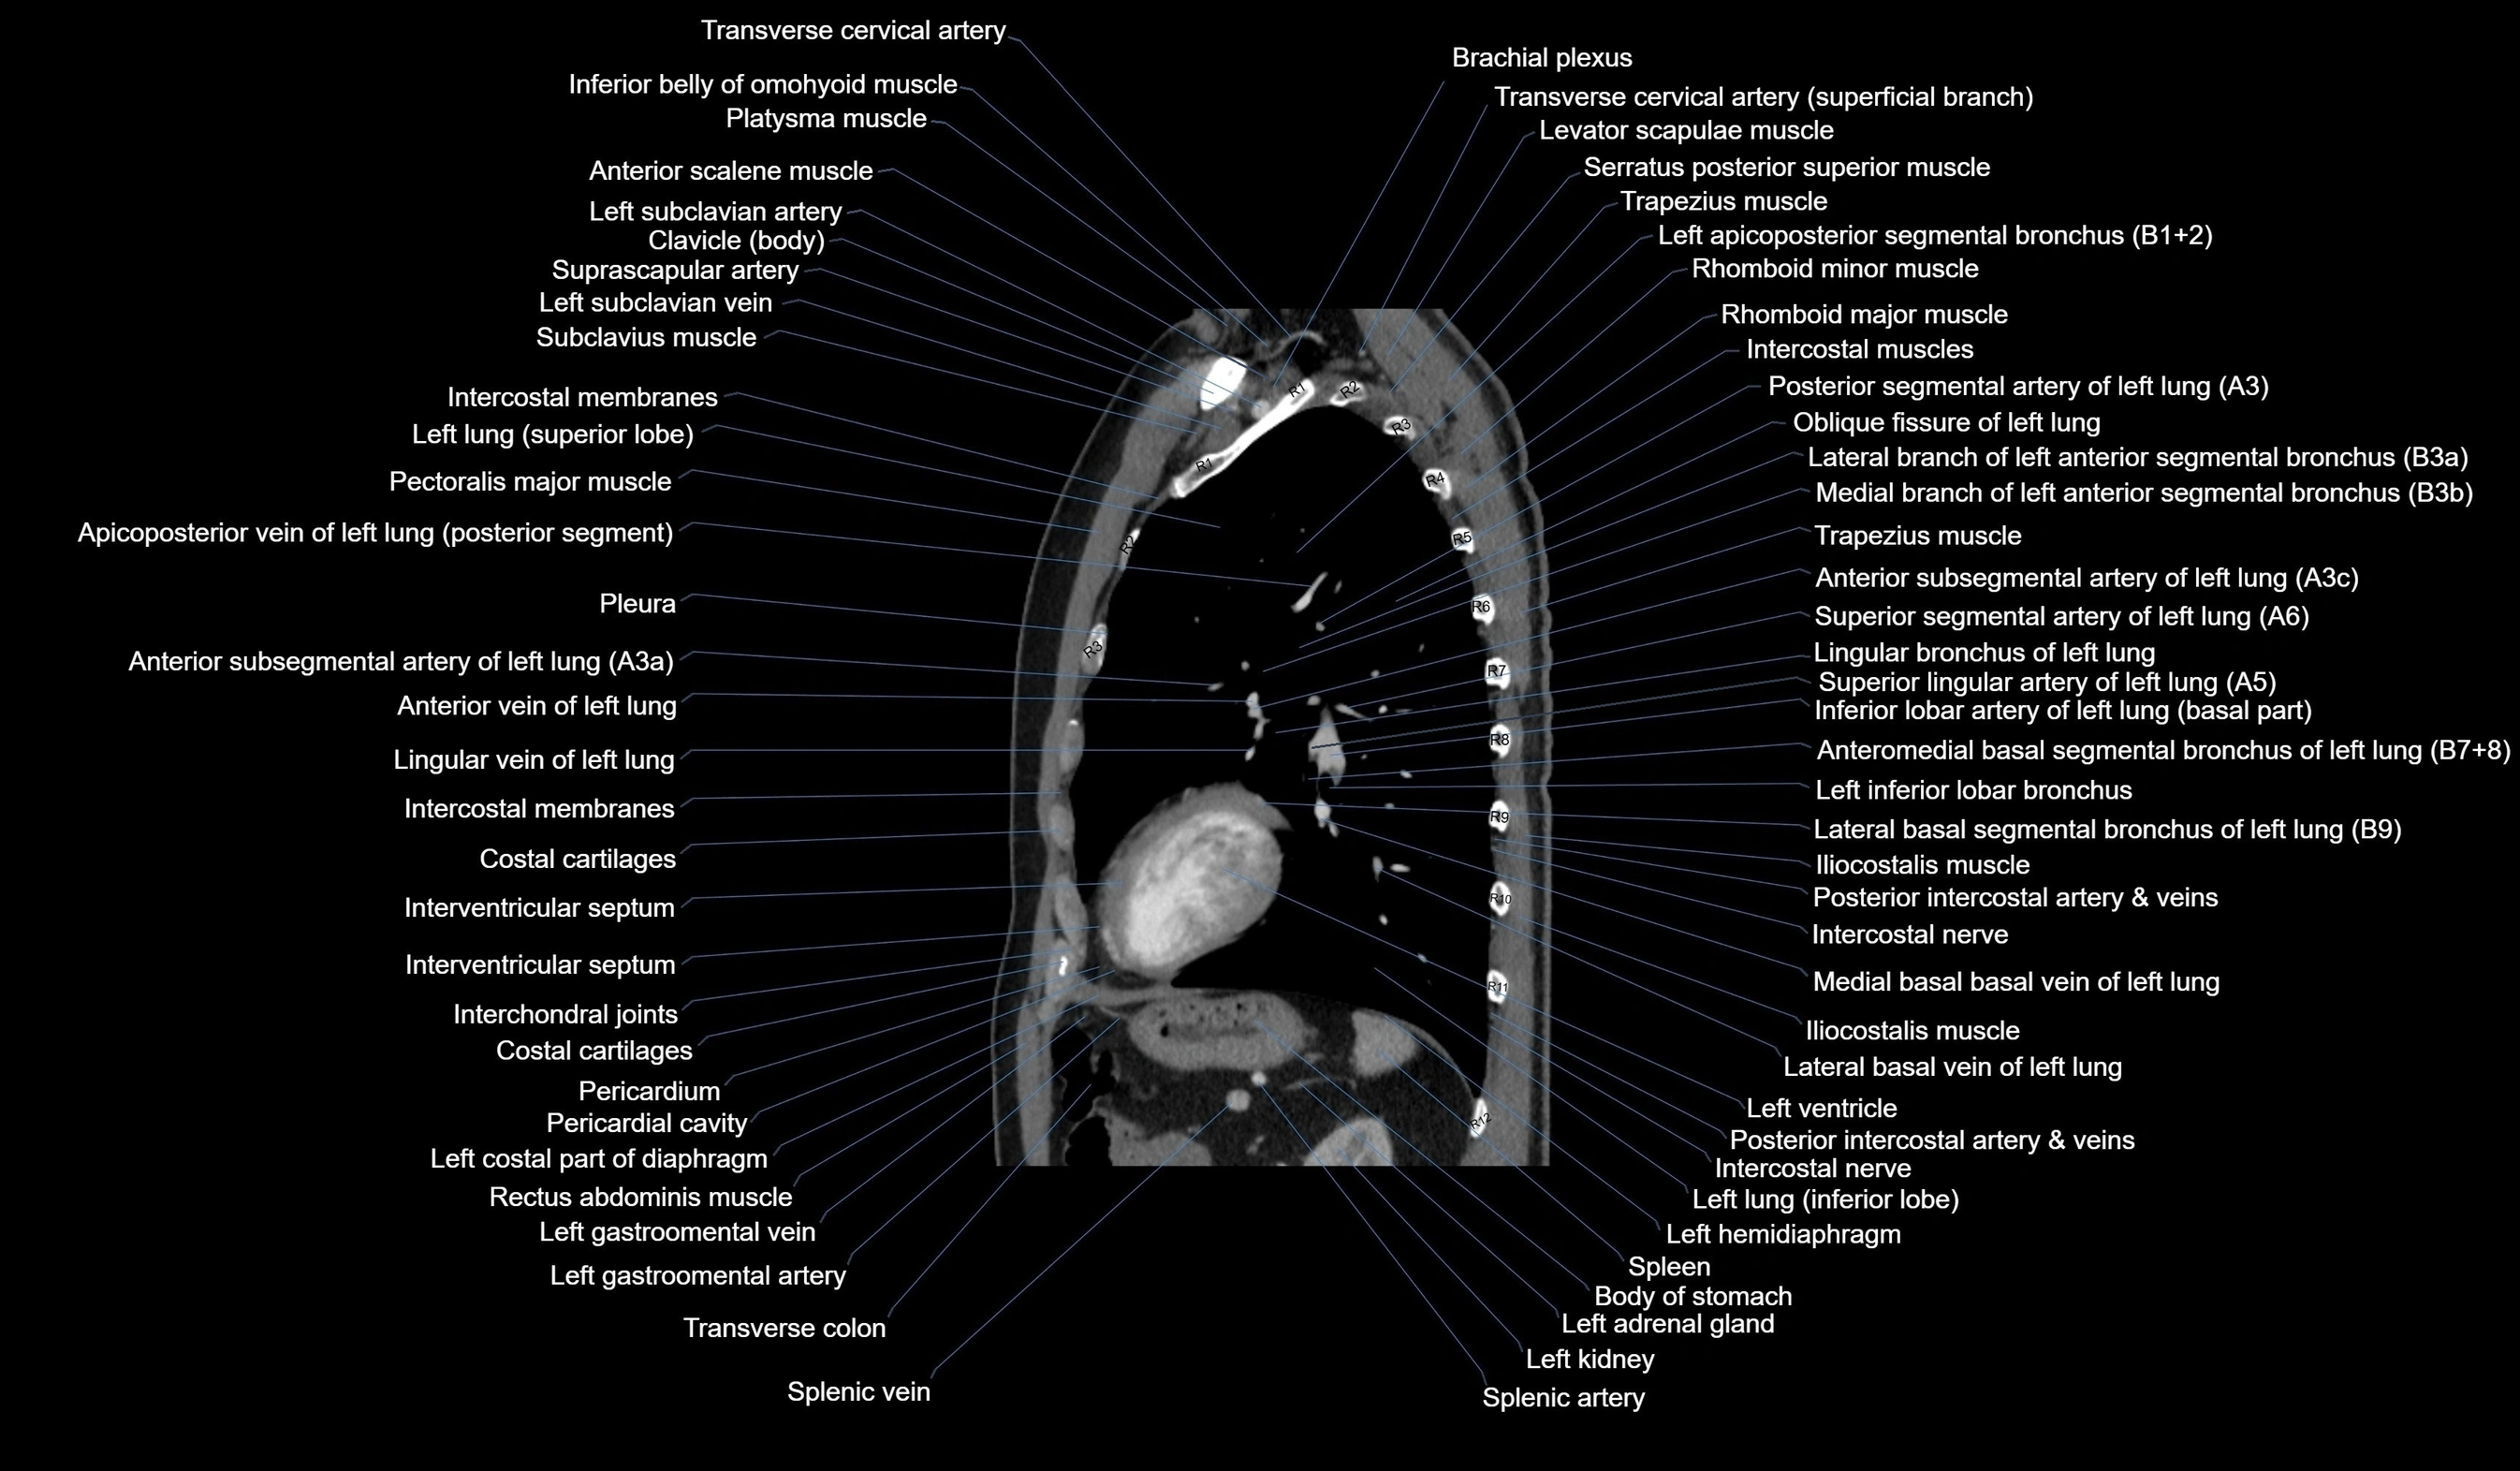

- Brachial plexus

- External oblique muscle

- Inferior lingular bronchus of left lung (B5)

- Lateral basal segmental bronchus of left lung (B9)

- Left anterior segmental bronchus (B3a, B3b, B3c)

- Left apicoposterior bronchus (B1+2a, B1+2b)

- Left common carotid artery

- Left gastro-omental (gastroepiploic) vein

- Left hemidiaphragm

- Left inferior lobar bronchus

- Left lung (inferior lobe)

- Left subclavian artery

- Left subclavian vein

- Lingular bronchus of left lung

- Oblique fissure of left lung

- Pectoralis major muscle

- Pleura

- Posterior segmental artery of left lung

- Splenic artery

- Splenic vein

- Subclavius muscle

- Trapezius muscle